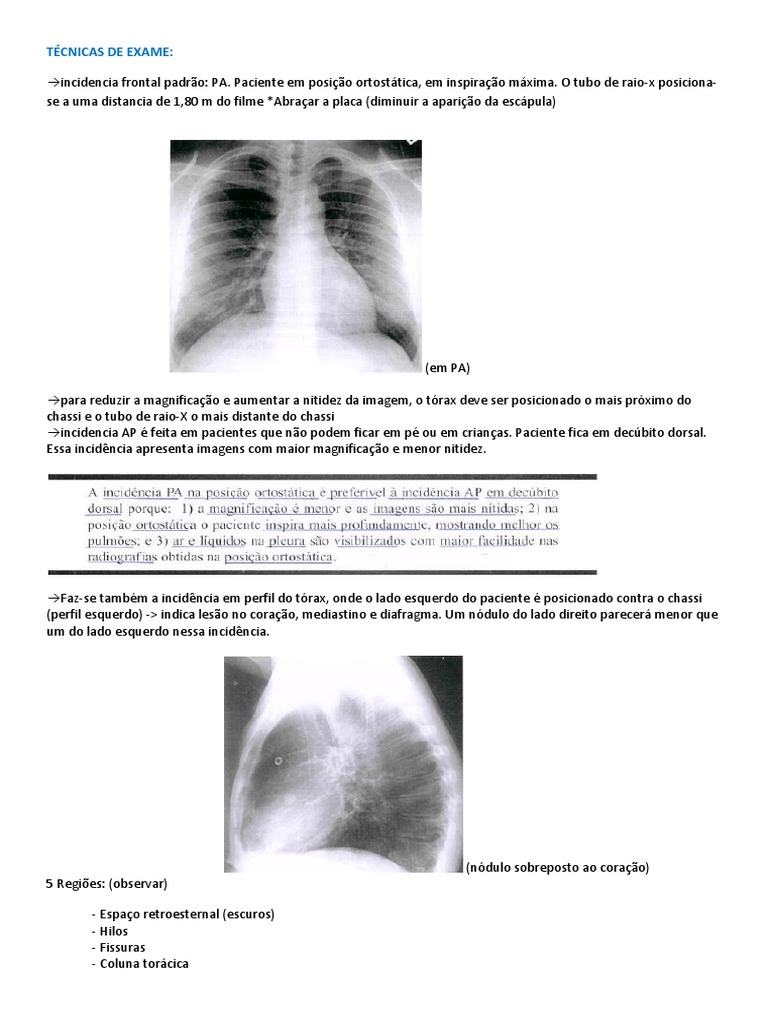

Tecnicas De Exame Coracao Pulmao